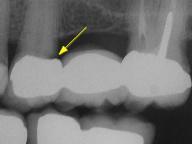

Recurrent decay (decay around existing fillings) can be detected during recall exams. If left untreated, the decay will spread underneath the filling and the tooth may require extensive treatment.

Regular x-rays help to find problems that may not be visible. Decay has been found underneath this bridge (yellow arrow). If left untreated, the tooth and the entire bridge may be lost.

Bone loss around an implant may also be found on an x-ray (yellow arrow). This type of bone loss is not painful, but if left untreated, the implant may be lost.